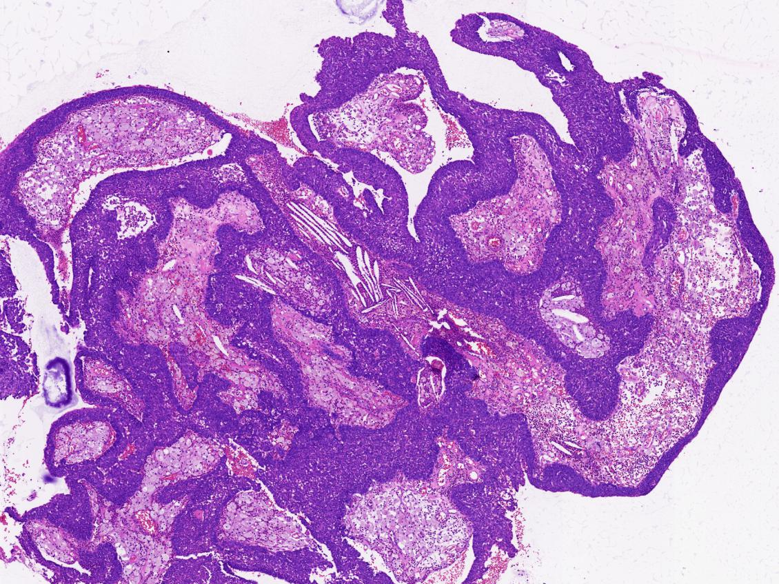

病理特征:宽薄乳头、 迷宫样内翻生长、单一肿瘤细胞形态、棘层松解、显著中性粒细胞浸润;

可见:细胞旋涡、透明细胞变、微囊形成、黏液纤毛上皮帽、部分肿瘤细胞异型性增加、坏死。

1、内翻性乳头状瘤:乳头结构简单、圆形,巢中央常形成囊腔,细胞成分复杂,包括鳞状细胞、纤毛柱状细胞和杯状细胞,可通过分子检测及AFF2 免疫组化鉴别。